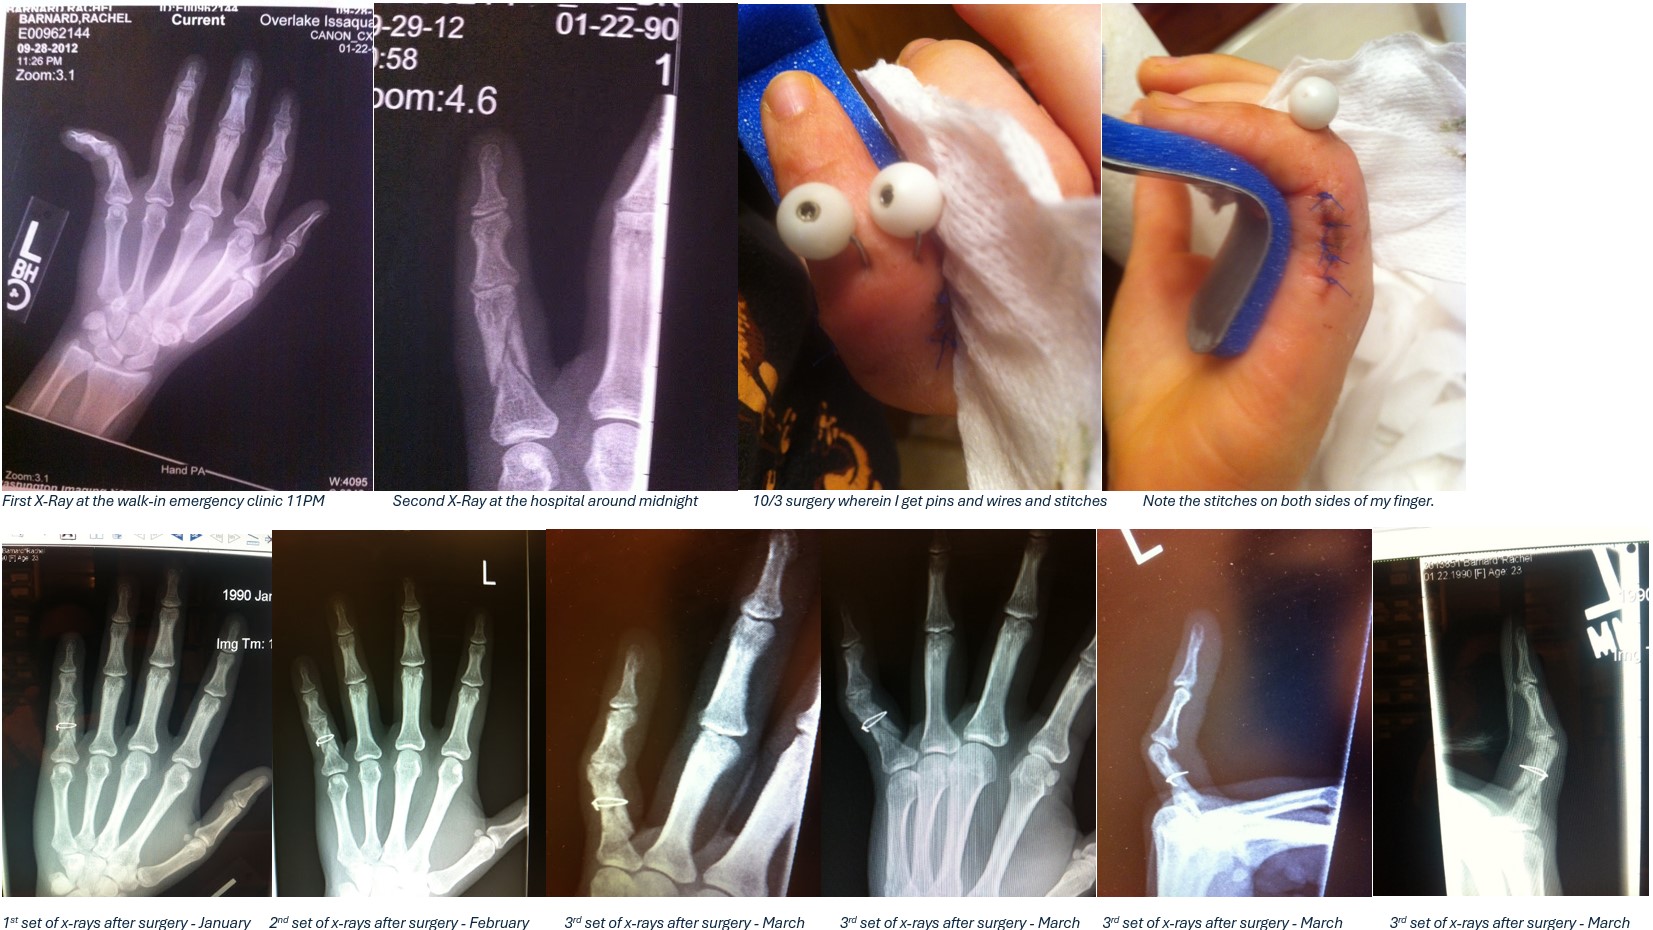

Revenge of the Finger

One Friday night in late September Rachel was out playing dodge ball in Seattle. She reached out to catch a flying ball but missed. Looking down she noticed something was amiss. Her finger was crooked! Cursing her ill luck she left the playing field in search of ice and so begins the saga of the pinkie finger…